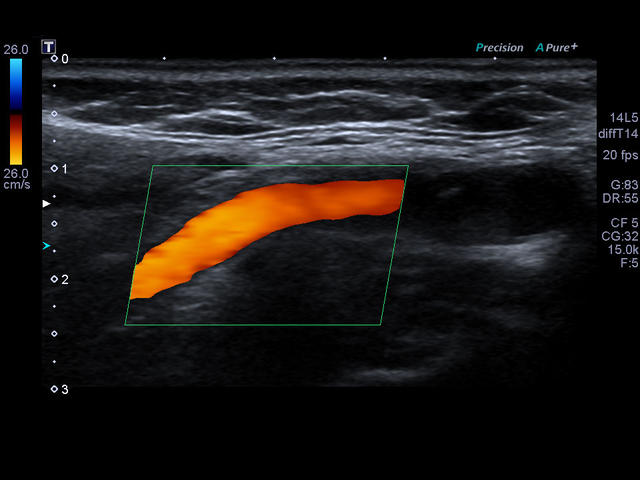

Xario 200 — это продуманная эргономика, впечатляющее качество изображения, отлаженный рабочий процесс и предельно высокая компактность. В Xario 200 цветовая доплеровская визуализация вышла на качественно новый уровень. Полностью интегрированная система управления данными пациентов и изображениями системы Xario обеспечивает удобный просмотр и простое управление исследованиями.

- Исследования сосудов

- Цветной, энергетический допплер - Colour Doppler Imaging/ Color Angio (CDI/CA).

- Высокотехнологичное сложное многолучевое сканирование с режимом подавления спекл-шумов в реальном времени - Aplipure plus.

- Одновременная обработка множества смежных ультразвуковых линий Precision Imaging